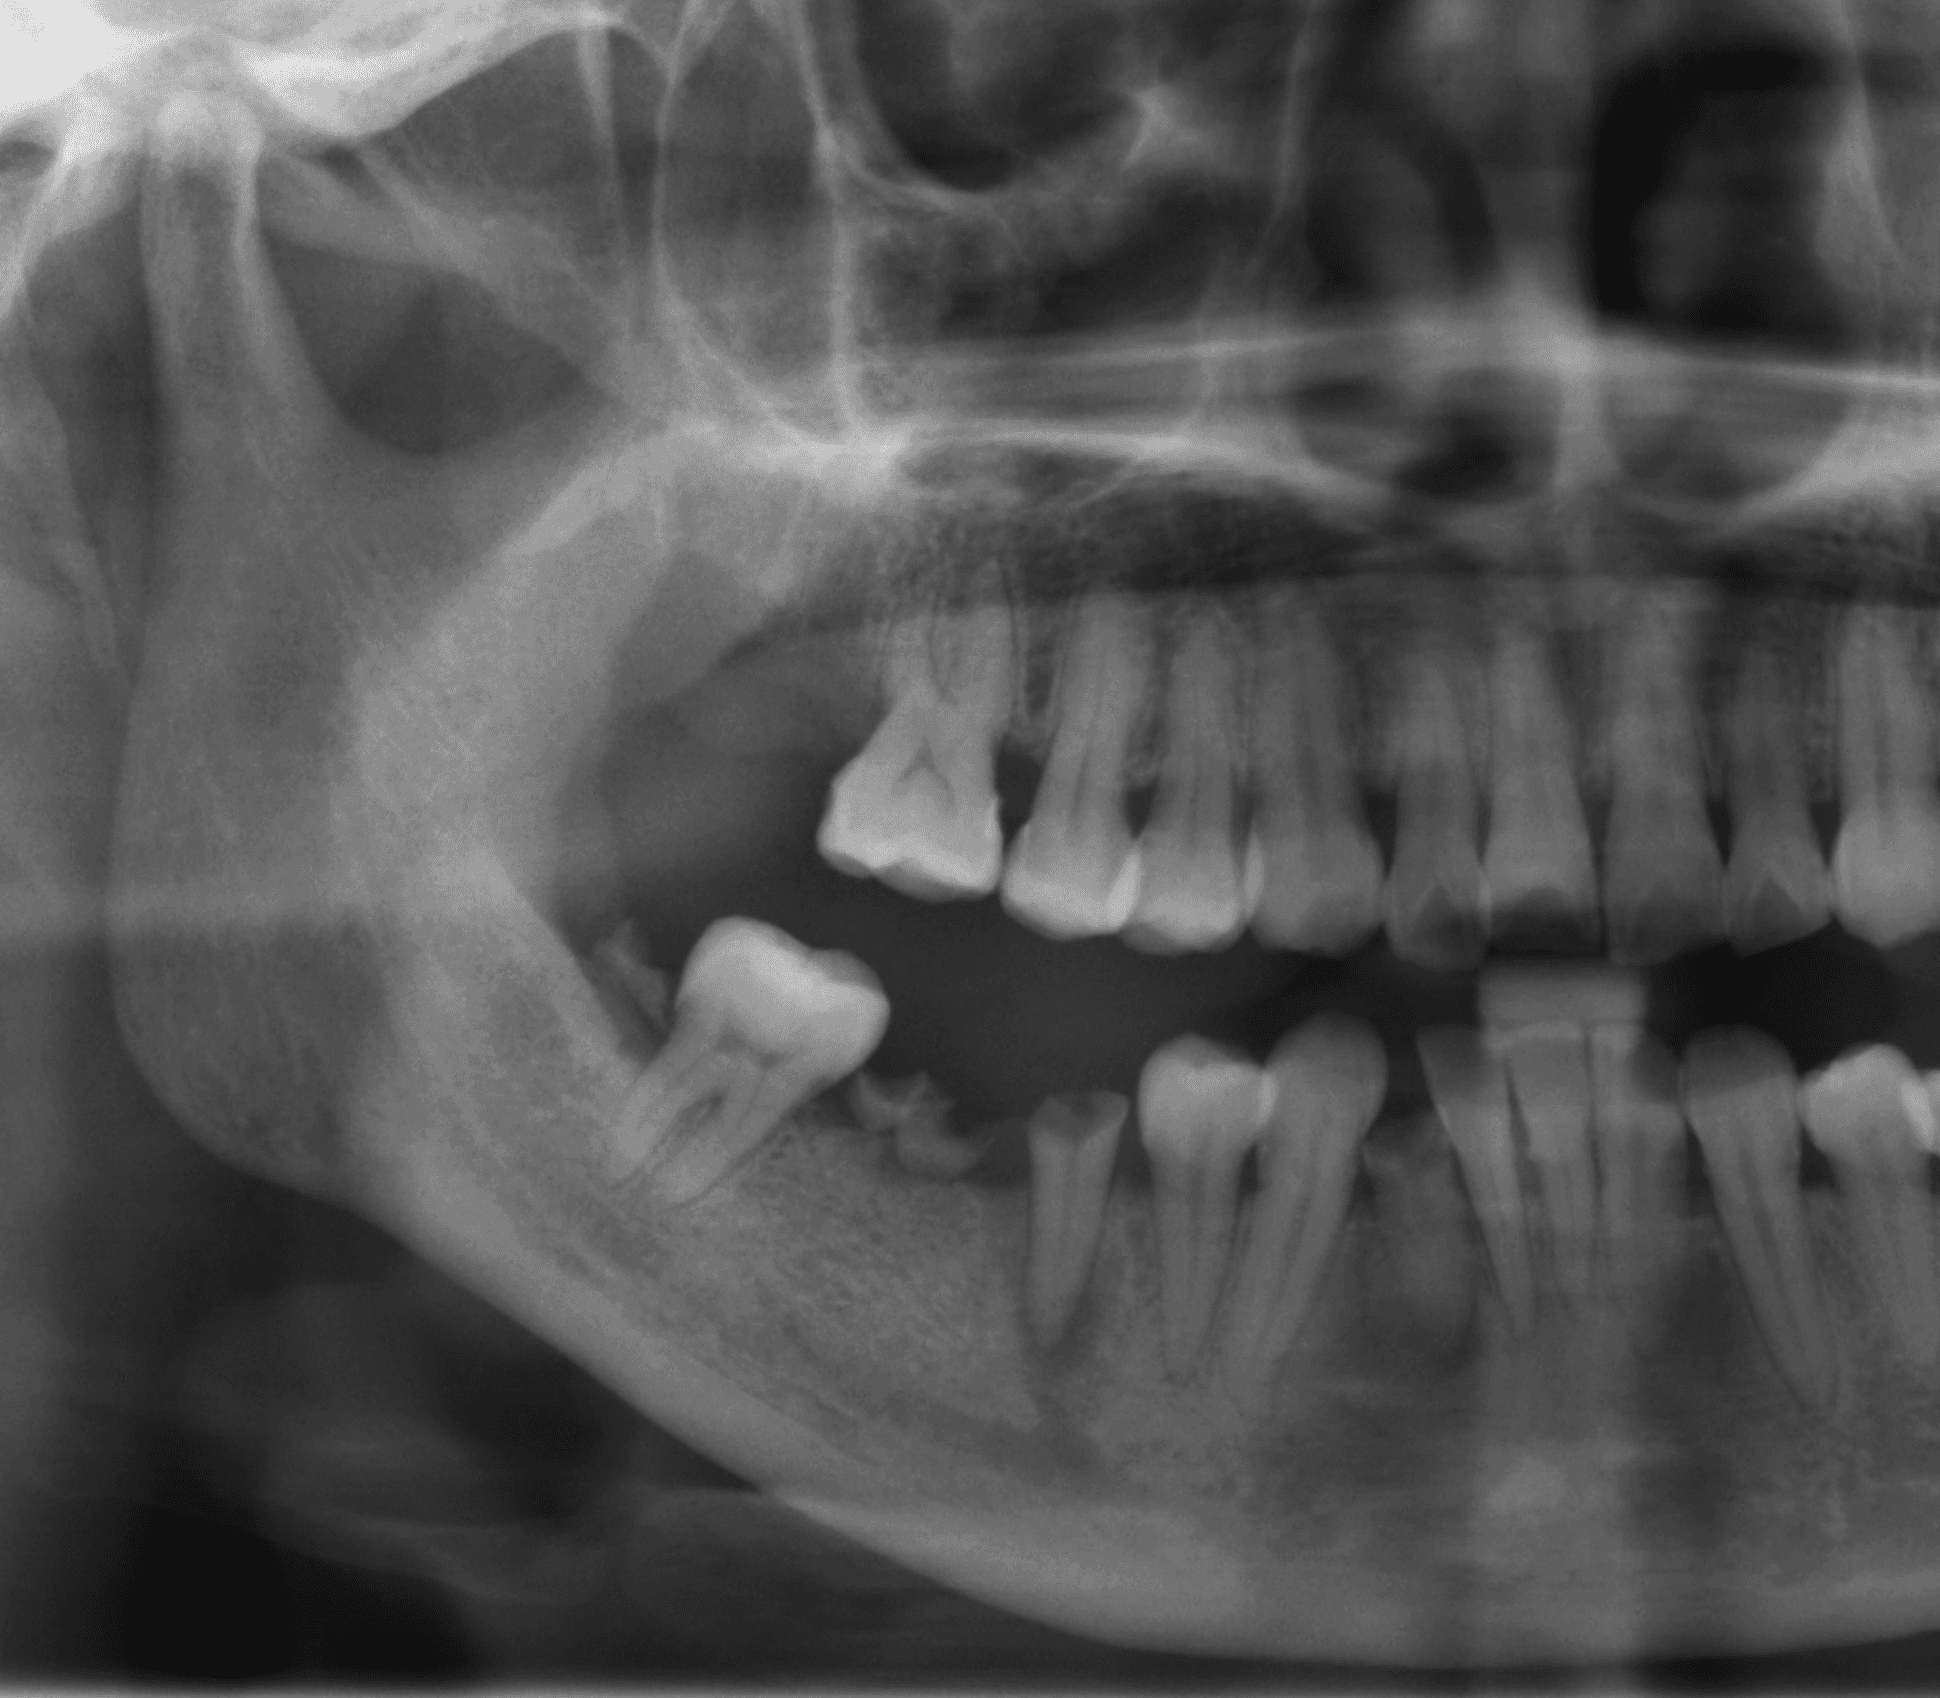

Diagnostic assisté par IA

Gagnez un précieux temps lors de vos consultations. L'IA de SmiloLink identifie automatiquement les caries, les lésions apicales et d'autres pathologies sur vos radiographies panoramiques et rétroalvéolaires.